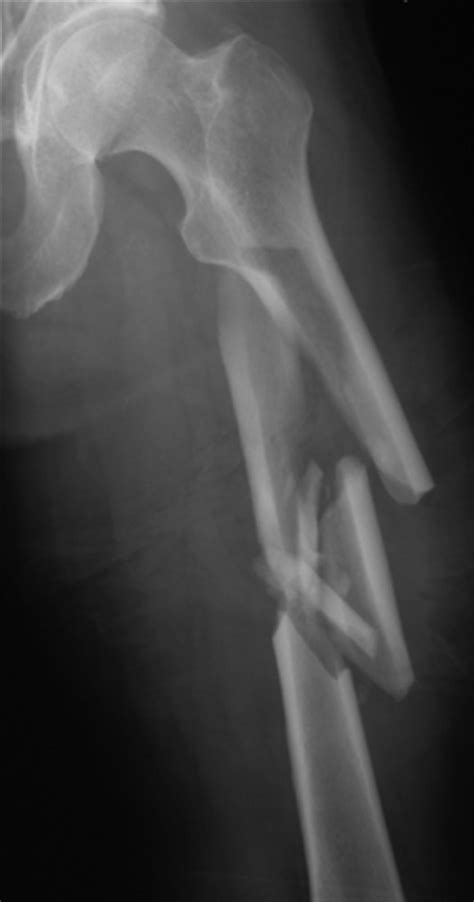

Following the surgical repair—typically involving intramedullary nailing, plates, or screws—the first few weeks are focused on stabilization and pain management. During this time, the body initiates the "inflammatory phase" of healing, where blood clots form and the body begins to clear away damaged tissue. It is critical to follow the surgeon’s weight-bearing restrictions strictly, as putting pressure on the leg too soon can displace hardware or interfere with bone union.